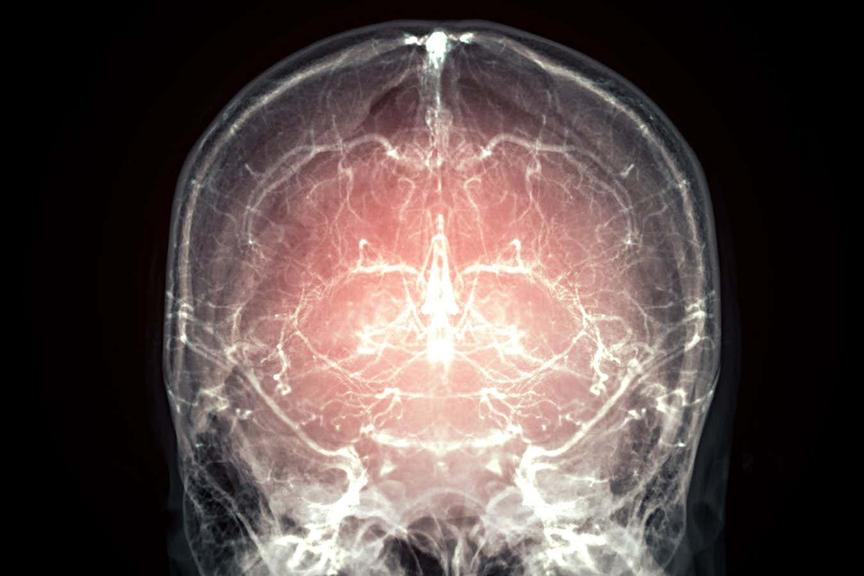

A pig's brain has been frozen with its cellular activity locked in place and minimal damage.

Some believe the same could be done with the brains of people with a terminal illness, so their mind can be reconstructed and they can "continue with their life"